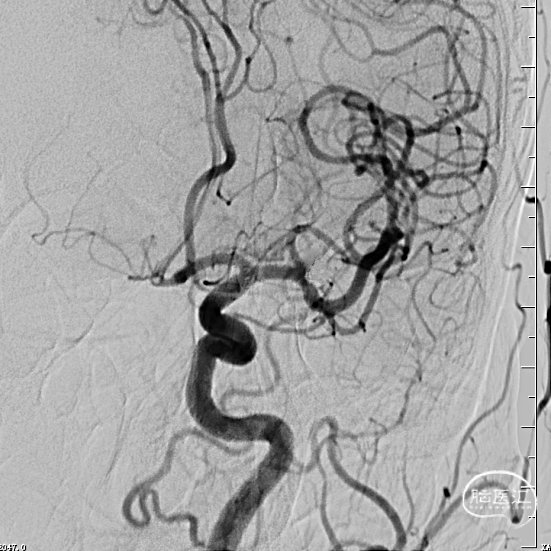

术后6个月复查造影示:弹簧圈致密充填瘤体内,瘤体消失,左侧颈内动脉及大脑前、中动脉均显影良好,载瘤动脉通畅,形态和血管直径较动脉瘤栓塞前无明确变化。支架形态良好,未见移位及血栓形成。